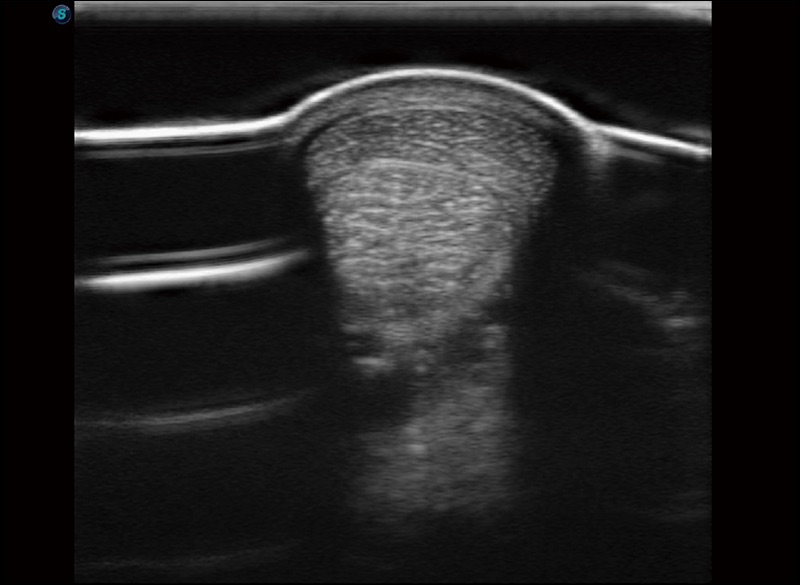

穿刺針增強(qiáng)

高清顯示穿刺進(jìn)針情況